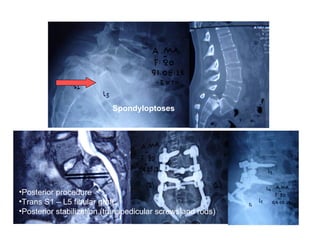

Spondyloptoses

•Posterior procedure

•Trans S1 – L5 fibular graft

•Posterior stabilization (transpedicular screws and rods)